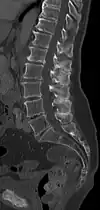

Sagittal CT of the lumbar spine showing Baastrup's sign.

The salient feature of the disorder is the exuberant osteophytosis that occurs at posterior lumbar spinous processes. Osteophytes are coarse calcifications at the edges of bone that form due to repetitive stress and trauma. There is also atrophy and fatty replacement of paraspinal musculature, which can be detected by CT or MRI.[5]